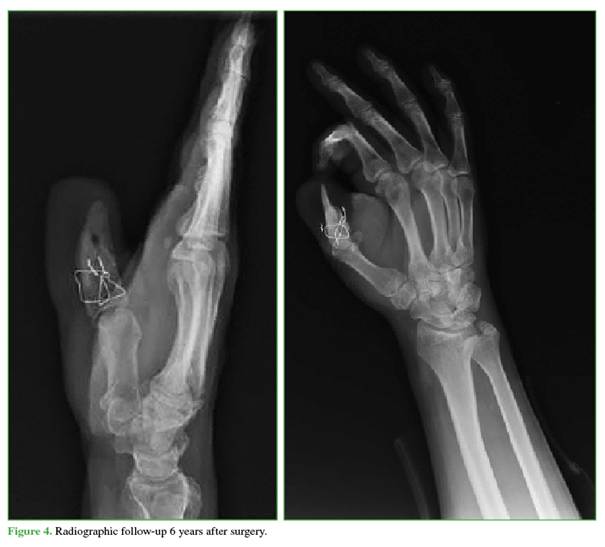

Radiographs show partial bone remodeling due to resorption, with a 10% loss of graft length, without clinical implications or fragility-related findings (Figure 4).

In the 6-year long-term follow-up, the results are favorable: the patient maintains significant functionality, is pain-free, and exhibits good adaptation to work and sports activities. These findings are consistent with published reports indicating that although osteoplastic reconstruction may result in partial loss of graft length due to bone remodeling, this generally does not compromise long-term function.4 In our case, the 10% loss of graft length had no significant clinical repercussions, reaffirming the robustness of this technique in providing long-term stability and functionality.